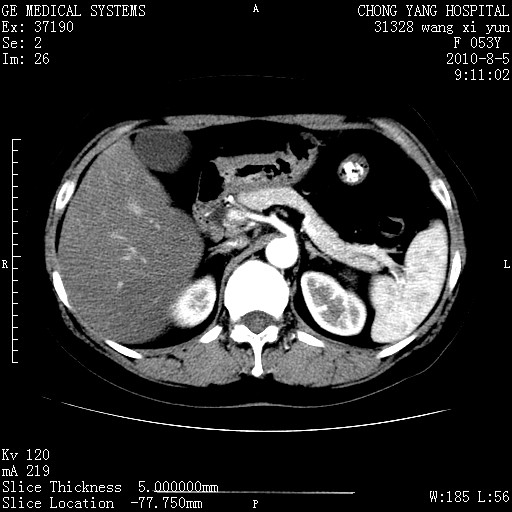

标题: CT28214:F41Y 血尿二十天,建议盆腔平扫加增强。

胆管细胞ca?

1)考虑肝左叶胆管细胞癌。2)脂肪肝。

支持胆管细胞ca。